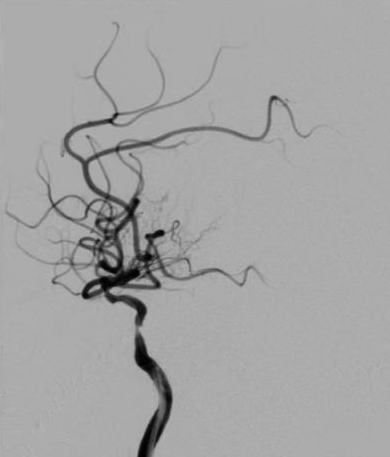

导丝怎么扩【载药时代 球扩天下】NOVA DES®颅内药物洗脱支架在颈内动脉颅内段重度狭窄中的应用体会二例!_https://www.jmylbn.com_新闻资讯_第17张

DWI

导丝怎么扩【载药时代 球扩天下】NOVA DES®颅内药物洗脱支架在颈内动脉颅内段重度狭窄中的应用体会二例!_https://www.jmylbn.com_新闻资讯_第18张

MRA

头颅核磁:颅内多发缺血灶;DWI未见明显高信号;灌注可见右侧半球低灌注

头颅MRA:右侧椎动脉闭塞可能,双侧颈内动脉末端、左侧椎动脉V4段重度狭窄可能。